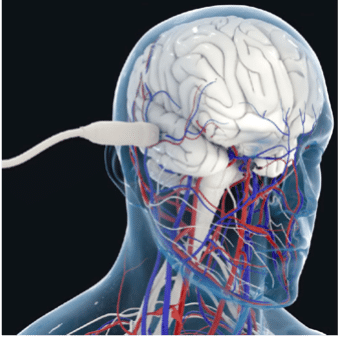

A key challenge in dealing with strokes is distinguishing between ischemic and hemorrhagic stroke as early as possible, as well as monitoring aneurysm. A promising approach to achieve this is transcranial imaging of deep vasculature (and quantification of hemodynamic parameters).

This is now possible in the adult human brain at microscopic resolution using ultrasound localization microscopy (ULM) of intravenously injected microbubbles. To take advantage of this concept, we’re developing a transcranial ULM scanner for stroke and aneurysm diagnosis in adults, in close collaboration with Geneva University and Physics for Medicine Paris.

In conjunction with Caen University Hospital, the Physiopathology and Imaging of Neurological Disorders (PhIND) group based in Caen, and Physics for Medicine Paris, we’re developing a small implantable probe using our ultrafast Doppler technology, with the aim of allowing continuous cerebral blood flow monitoring in several brain regions for brain-injured patients.